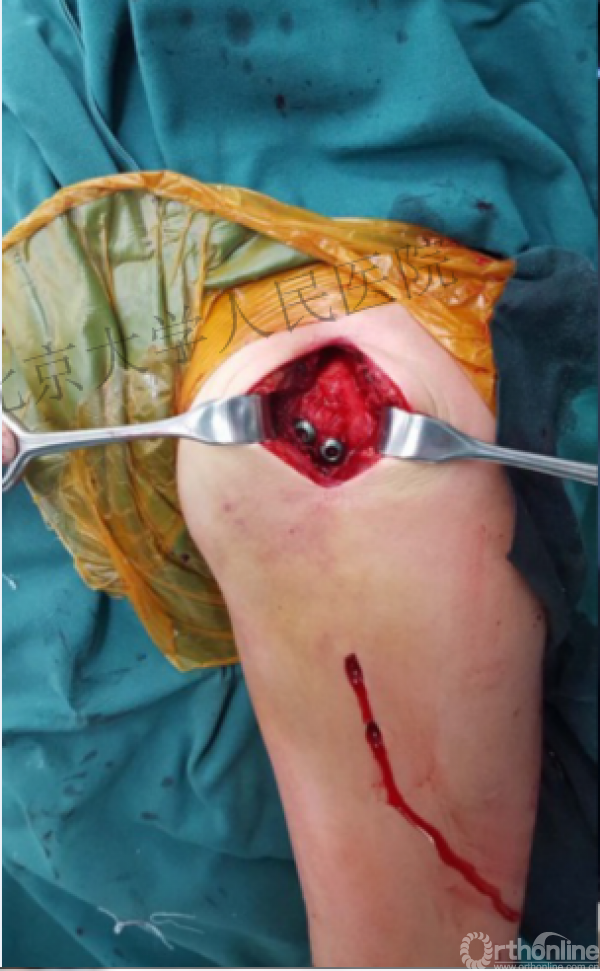

病例

可否有更好的进钉和复位的更好帮助办法?

进钉更完美——我们的帮助

术中片